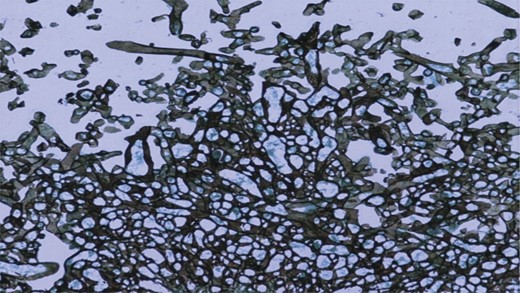

The patient was started on intravenous piperacillin tazobactam and was subsequently taken for emergency debridement of the wound on the right shoulder. During surgery, as the wound was being debrided, there was practically no bleeding (Fig. 3). There was extensive necrosis involving the scapular, neck and facial muscles, although the subcutaneous tissue and the overlying skin looked apparently normal. The tissue was sent for histopathology and, to our surprise, it turned out to be positive for fungal elements. Examination showed acute on chronic inflammatory cell infiltrate, necrosis and splaying of muscle fibres. Many broad aseptate fungal elements morphologically resembling features of the zygomycetes group were seen (Fig. 4). Special staining on periodic acid Schiff (PAS) stain also showed clusters of broad aseptate fungal hyphae.

PAS stain showed clusters of broad aseptate fungal hyphae. (10× magnification).